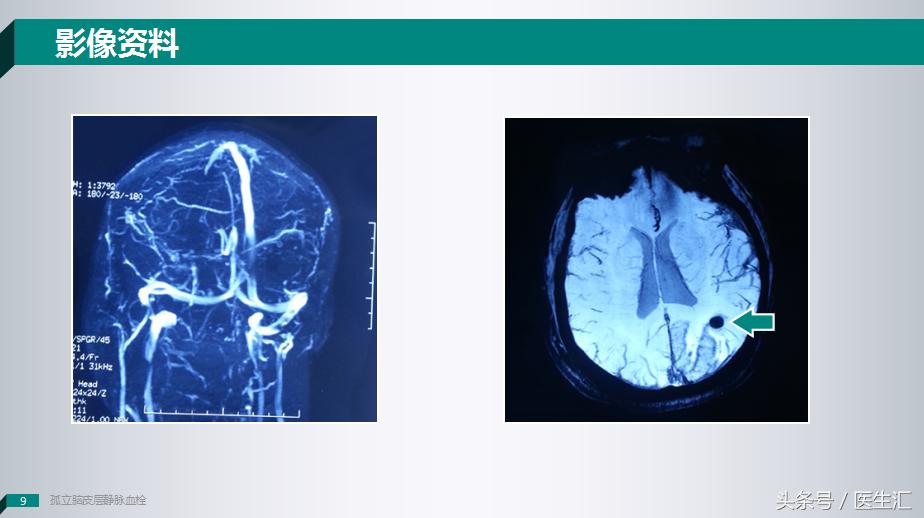

T1像上有一个长T1信号,但是这个长T1信号和T2信号和常见的脑梗死病灶并不是很相似,是沿着脑沟及脑回这样一个病变。

在弥散像上我们看到一个类圆形的小病变。

这个时候我们给患者做了一个SWI头颅磁敏感加权成像上提示这个病灶可能是一个出血的病变,但是我们给患者做MRV成像的时候却发现也没有什么问题。